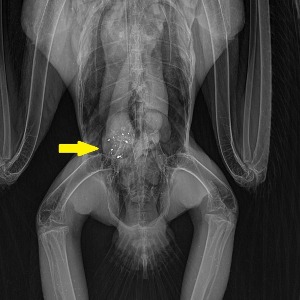

Photo: x-ray of a bald eagle shows lead fragments in stomach. @BRWC 2019

Subsequent bloodwork revealed lead levels in the blood of 27 micrograms per deciliter. What is the normal or healthy amount of lead expected to be found in any animal's blood? Zero.

Unfortunately, this scenario is not uncommon, as more than 90% of adult eagles brought to our center have traces of lead in their systems.

While trauma remains the primary reason for eagle admissions, even low levels of lead can compromise their ability to navigate and react swiftly, making them more susceptible to vehicular collisions or other life-threatening situations.